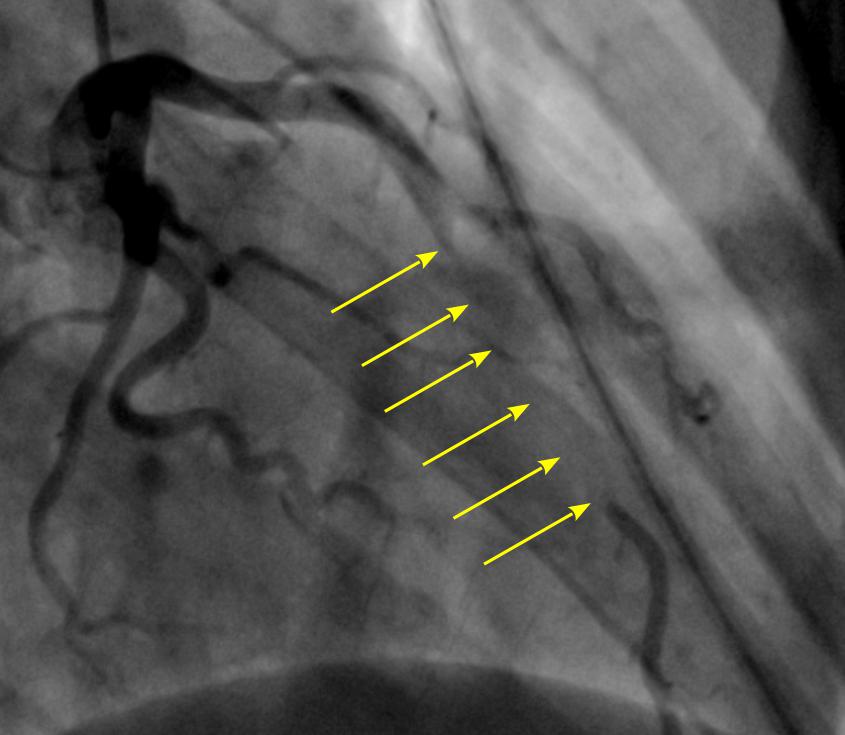

На рисунке приведена коронарография пациента до операции. |

«Коронарные сосуды в норме находятся на поверхности сердца — они окутывают его сеточкой, находясь на поверхности, не проходя глубоко в мышцы. А тут часть сеточки была под мышечным мостиком. Данная врожденная патология проявилась с ростом мальчика и увеличением мышечной массы сердца. Это очень редкое заболевание — за 31 год работы детским кардиологом я впервые столкнулась с таким диагнозом у ребенка. У взрослых пациентов он встречается, хотя тоже не часто. Хирурги Центра Алмазова удалили мостики, сжимавшие нормально сформированные коронарные сосуды. После операции, выполнив контрольную коронарографию, врачи увидели нормальное коронарное русло без сужения просвета во время сокращения сердца», — рассказывает лечащий врач Татьяна Николаевна Макушкина.